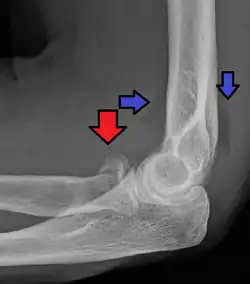

| Radial head fracture (red arrow) with posterior and anterior sail sign (blue arrows) | |

Radial head fractures are diagnosed from a clinical assessment and diagnostic imaging.[7] Symptoms may include pain or tenderness at the radial head, bruising, swelling, and a limited range of motion of the injured elbow.[2] Diagnostic imaging may include ultrasound, plain radiography (x-ray imaging), Computed tomography scan (CT), and magnetic resonance imaging (MRI).[2][4] A fat pad sign may be present on diagnostic imaging and may indicate a radial head fracture.[5]

CT scan showing a radial head fracture -

Radial head fracture seen on 3D CT reconstruction